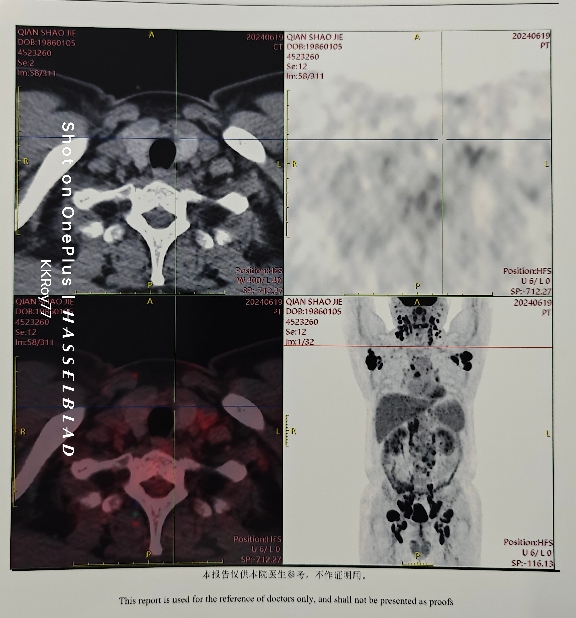

确诊滤泡,各位大神们,帮忙看一下, petct 出来了。

核医学科医生有点懒,没有给出具体尺寸,从图上来看,可能符合治疗指征了。

大小也没有明确,会不会在医生那里的 petct 版本会看的仔细一点。范围有点大。您说,我再看几家医院应该不会算是耽误治疗吧。

感觉肝有点大?淋巴结大小接近大包块了。大概率要住院治疗,可能要始终吃恩替卡韦